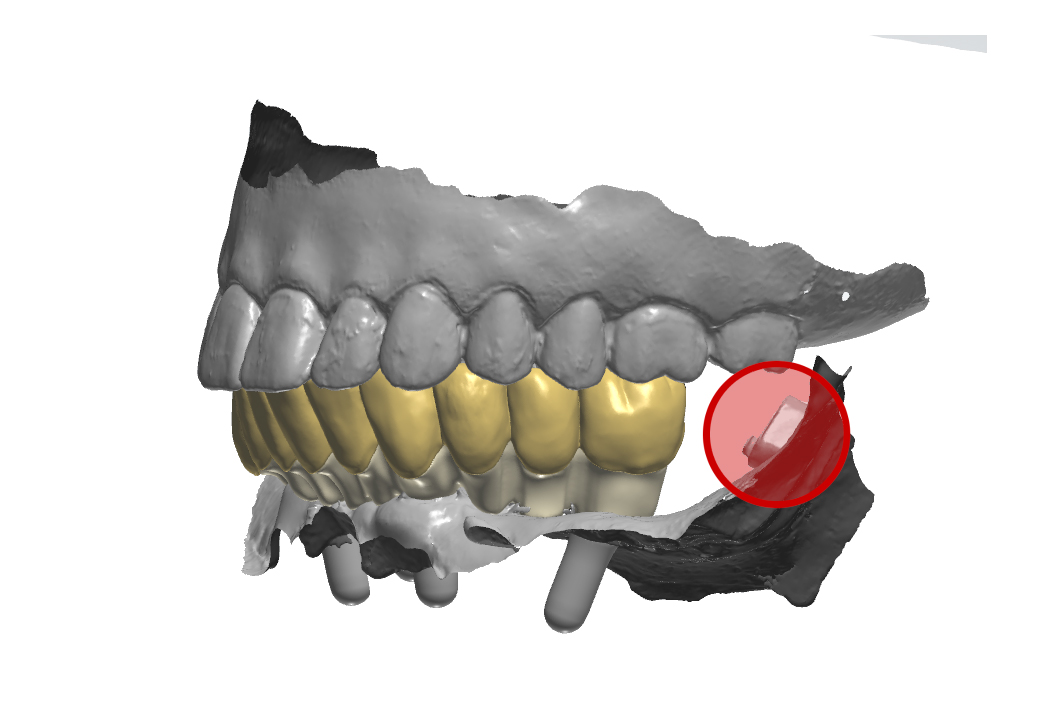

Arcate scansionate all’interno dell’articolatore digitale

Fig. 8. (b) Arcate scansionate all’interno dell’articolatore digitale, in evidenza gli ScanSke.

Prospettiva frontale della protesi progettata

Fig. 9. (a) Prospettiva frontale della protesi progettata in base all’occlusione abituale della paziente

Prospettiva dall’alto della protesi inferiore

Fig. 9. (b) Prospettiva dall’alto della protesi inferiore, in evidenza gli Scan Ske.

Prospettiva laterale sinistra della protesi in occlusione

Fig. 9. (c) Prospettiva laterale sinistra della protesi in occlusione, in evidenza gli ScanSke.